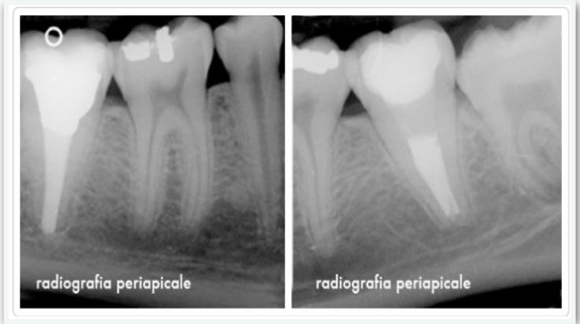

RADIOGRAFIA ENDORALE

La radiografia endorale, permette all’odontoiatra di avere info specifiche riguardanti una zona circoscritta delle arcate dentarie, in genere di 2-3 denti al massimo.

La radiografia endorale periapicale ci consente di visualizzare in maniera completa e dettagliata il dente e i suoi tessuti circostanti. Con essa siamo in grado di fare diagnosi di carie, malattia parodontale, ascessi, cisti, frattura dentaria, denti inclusi.